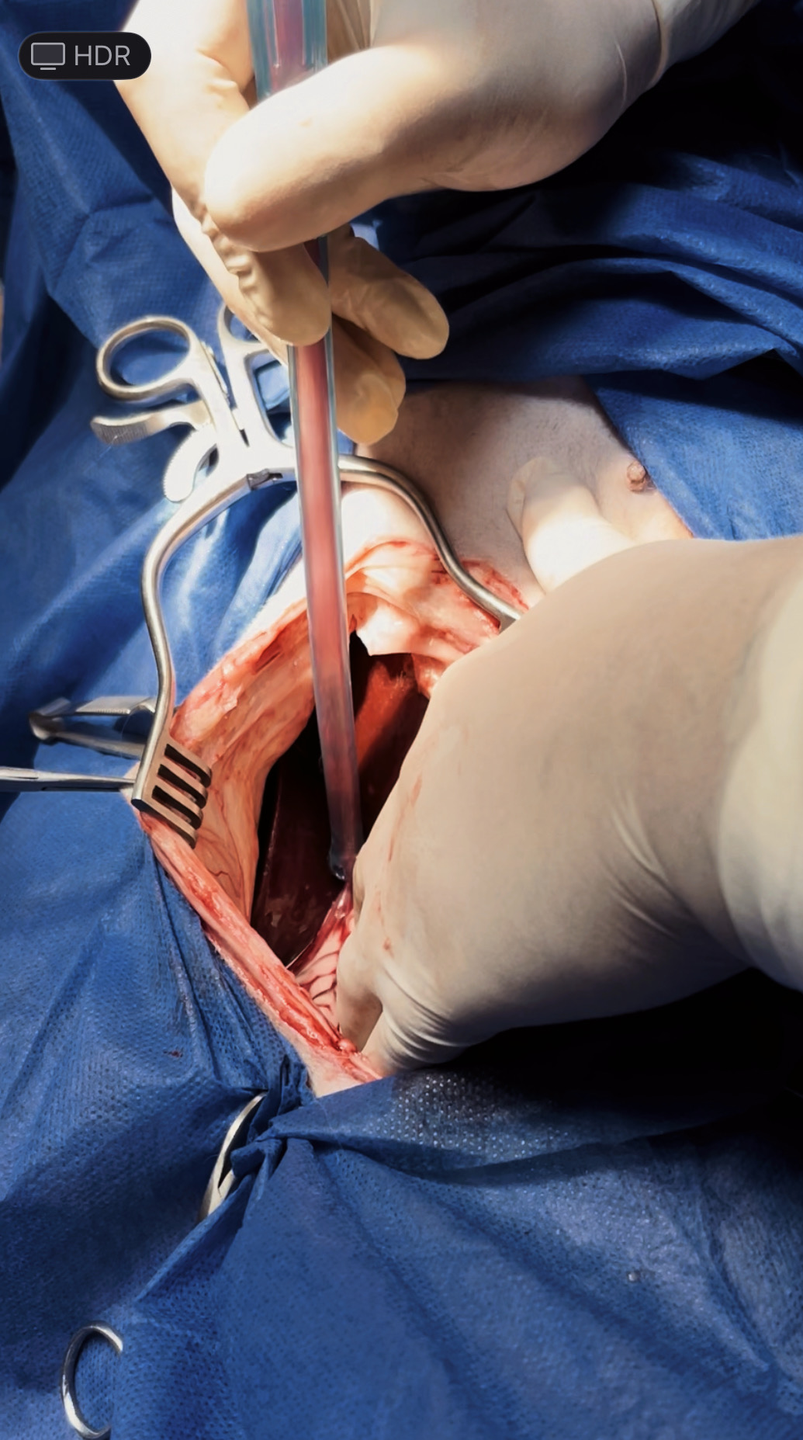

Surgery

The standard of treatment for splenic hemangiosarcoma's that have not yet metastasized to the lungs consists of surgery to remove the measurable (bulky or visible) disease followed by chemotherapy to delay the progression of metastatic disease